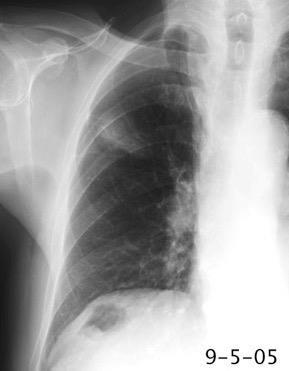

Masa axilar izquierda y derrame pleural derecho. Implantes pleurales, paraespinales . Ganglios en mamaria interna. Linfoma B difuso

Jaffe ES. Diagnosis and Classification of Lymphoma: Impact of Technical Advances.

2005. Masa pulmonar.